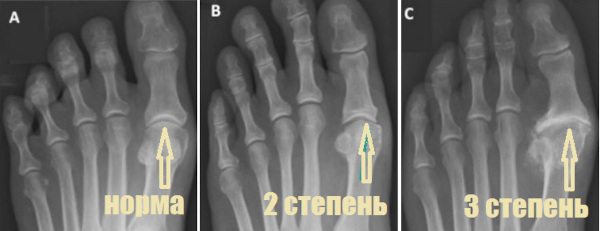

Существуют 3 стадии развития патологии:

- Начальная. Во время движений в ступнях возникает умеренный болевой синдром, также может присутствовать незначительный хруст. Инструментальная диагностика не сможет установить патологические изменения. В данном случае требуется МРТ для определения незначительных деформаций.

- Развернутая. Болевой синдром будет более выраженным, а походка шаткой, при этом будет проблематично передвигаться без опоры. Симптоматика синовита может возникать и проходить самостоятельно. Если сделать рентген, на изображении будет заметно увеличение остеофитов.

- Деформирующая. В состоянии покоя будут присутствовать болезненные ощущения, подвижность конечности будет нарушена, ступня поменяет форму, при этом часто возникает растяжение связок с подвывихом. На рентгеновском снимке будет отсутствовать щель сустава, при этом поверхности суставов будут сращены. На данной стадии пальцы почти не поддаются сгибанию, изменение формы и появление остеофитов будут выраженными.